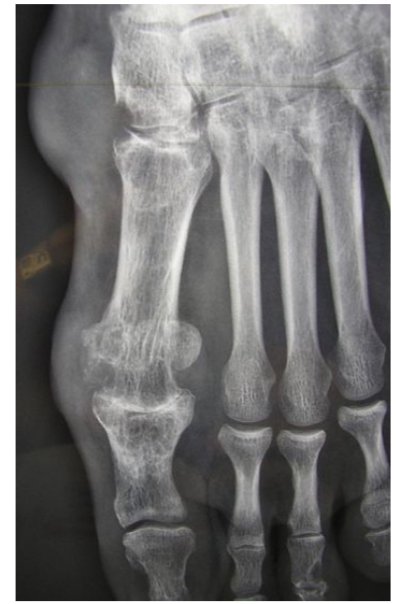

Goutte chronique

pincement global +condensation 1ere MTP

Érosions

Infiltration des parties molles